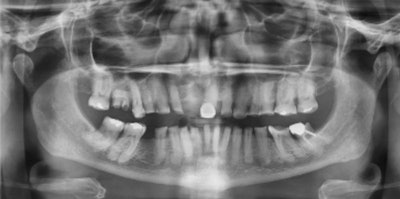

A 71-year-old woman presented to our office with significant anxiety. According to her, her father, while serving in the U.S. military, died in a dental chair. She suffered from intense dental fear her entire life as a result. Images and captions courtesy of Dr. Ankur Gupta.

After a thorough dental exam, a radiographic exam, and a review of her history and objectives, we determined that all of her remaining teeth should be extracted and replaced with an implant-retained overdenture. Judging by her radiographs, I anticipated that the extractions would be difficult and time-consuming. She refused to be “put to sleep” for the procedure.